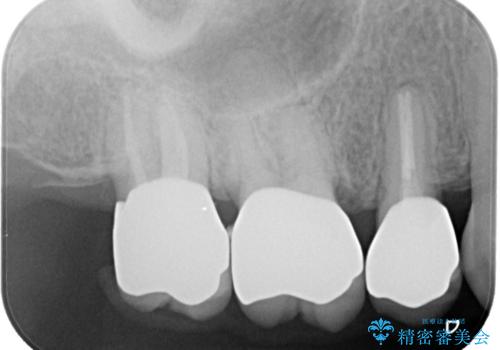

- 古い被せ物をやり変えたいことを主訴に来院されました。

根管治療も行い、きれいな被せ物になり患者さんも喜んでいました。

3本まとめて治療をすることで来院回数を減らし、患者さんの負担を減らすことができ喜んでいただけました。